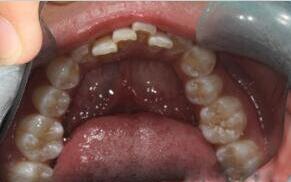

Celina,女,来自英国

现病史:上颌前牙轻度外翻

治疗方案:经过专业正畸医生检查后,制定陶瓷自锁托槽矫正方案。患者及家属同意矫正方案

优势:兼具了美观与舒适的优势,同时也具备了自锁托槽的高效快速排齐、轻力无痛的特点

五个月后牙齿排列整齐,患者表示满意!